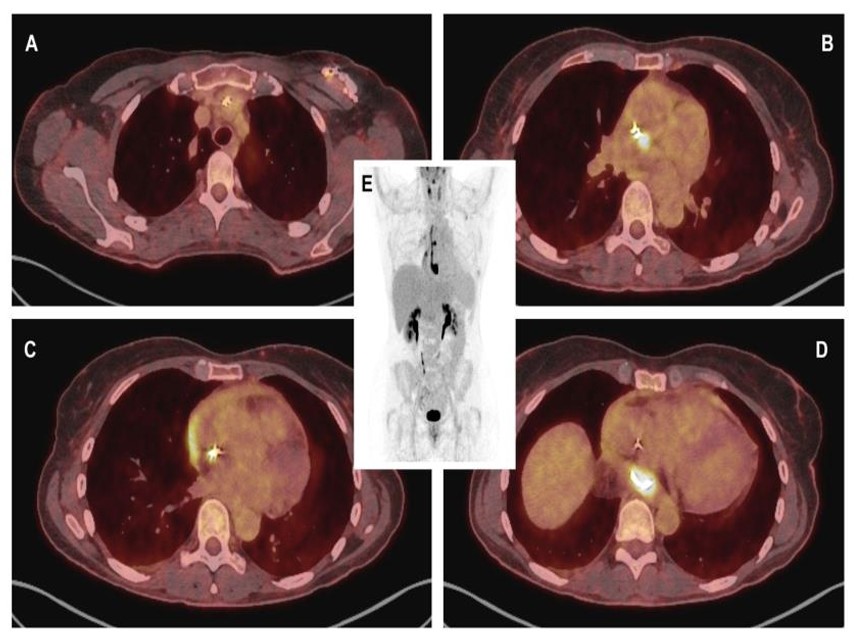

Fused CT-PET with 18F-FDG images (A) showing slight metabolic activity at the lead exit point, with more intense uptake from the entrance into the innominate vein extending to its distal end; (B) exhibiting greater focality in the middle third; and (D) demonstrating the region of the paraesophageal pericardial abscess, with a maximum standardized uptake value (SUVmax) of 16. (C) A thin line of activity was observed in the pericardial effusion, more intense in the region adjacent to the right atrium. (E) Volumetric PET reconstruction demonstrates the previously described findings.

Positron emission tomography with 18F-fluorodeoxyglucose (18F-FDG PET) was performed, which confirmed the suspected diagnosis, demonstrating infection of the generator and leads with involvement of the atrial wall and formation of a pericardial abscess (Fig. 3A-E). Both multiplex FilmArray testing and blood cultures remained negative after 14 days.